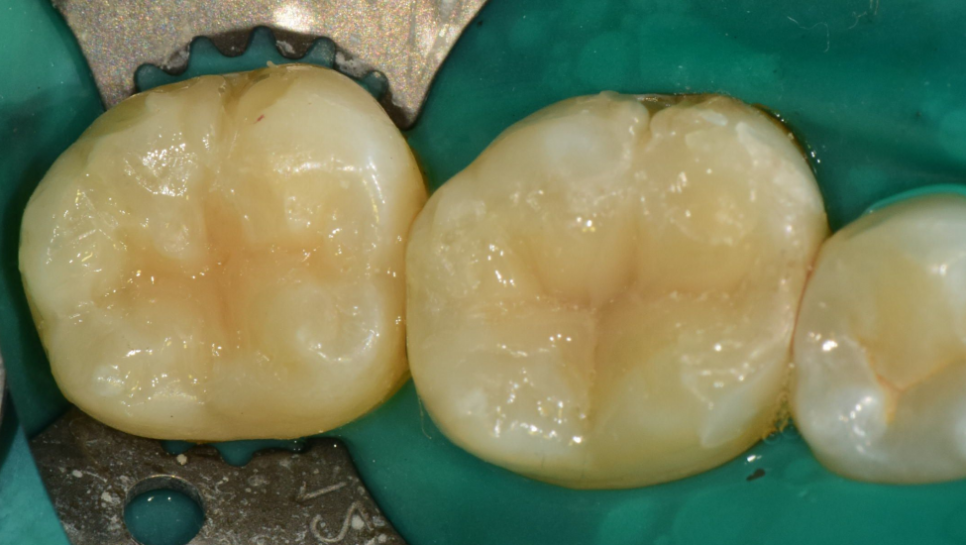

복합레진을 이용한 수복치료 시 치아 본연의 외형을 재현하려 노력합니다.